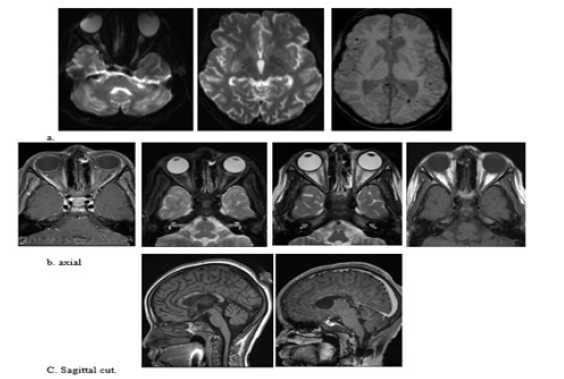

ID team consulted regarding positive TB interferon-gamma release assay and negative TB PCR, TB AFB, and TB culture; their impression was latent TB and prescribed upon discharge isoniazid and pyridoxine; however, she never received as per mother because they did not find pyridoxine. So, the initial impression was Latent TB, possible immune deficiency (not confirmed). Although no clear explanation of her skin ulcer and previous weakness of lower limb which improved in her second admission and, based on the initial assessment by Rheumatology not typical for autoimmune disease presentation but cannot rule out, consider repeat her blood work up later. A few months later, she presented with a sudden loss of vision. Admitted with a provisional diagnosis of optic neuritis. MRI brain done showed Figure 1.

A and c image: Interval resolution seen right basal ganglia and left frontal high FLAIR signal intensity lesions. bilateral cerebral multiple scattered cortical areas of drop of signal at susceptibility weighted images with involvement of the splenium of the corpus callosum and bilateral cerebellar hemispheres denoting micro bleeds.

Figure 1: Mild-to-moderate increased signal intensity of the optic nerves, chiasm and along the optic tracts, associated with increase enhancement of the optic nerves and chiasm indicating bilateral optic neuritis (image). Bilateral Edema of the intraconal fat more on the left side associated with mild increase enhancement along the optic nerve.

Comparing to the last study dated 30/12/2021 the current study revealed interval developed brainstem, left thalamic, left basal ganglia and left corona radiata area of high T2 and FLAIR(A), signal intensity showing restricted diffusion at DWI and corresponding low ADC(C), values with no enhancement after contrast administration. Interval resolution of previously seen right basal ganglia and left frontal high FLAIR shown in (B,C) signal intensity lesions. No appreciable changes regarding the previously seen corpus callosum and bilateral cerebellar lesions.

Again, seen bilateral cerebral multiple scattered cortical areas of drop of signal at susceptibility weighted images with involvement of the splenium of the corpus callosum and bilateral cerebellar hemispheres denoting micro bleeds. As seen in A and B. No intracranial enhancing abnormalities. The rest of the study shows no significant interval changes (Figure 3).